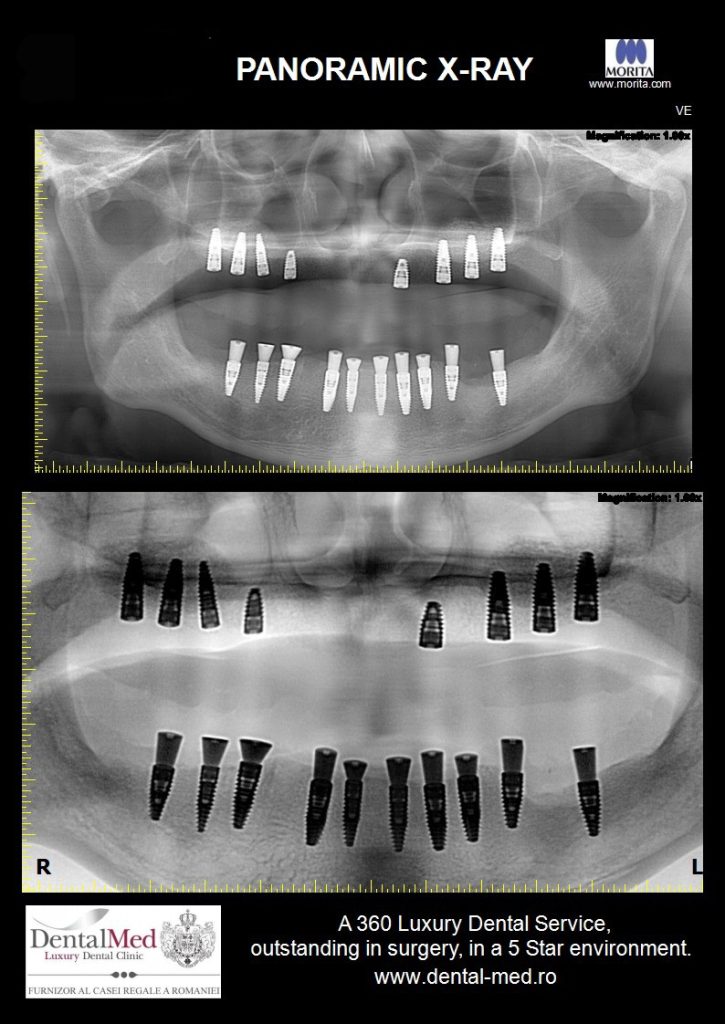

De obicei, acestora li se recomanda realizarea unei radiografii panoramice la fiecare 12 luni, pentru a determina masa osoasa prezenta in jurul implantului, dar pot fi indicate si tomografii computerizate 3D, fotografii de diagnostic etc.

Investigatiile imagistice permit depistarea din timp a problemelor invizibile clinic. Astfel, se poate interveni rapid, inainte ca pierderea osoasa sa devina ireversibila.